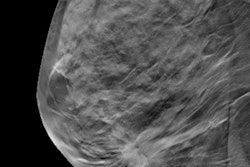

New York City Public Advocate Letitia James has called on New York City and the state of New York to expand access to digital breast tomosynthesis (DBT).

In a Tuesday press conference, James requested that NYC Health + Hospitals invest in DBT technology and for the state to add DBT to its Medicaid benefits package. She noted that while DBT technology is widely available in private hospitals in New York City, it's only available at one hospital in the NYC Health + Hospitals network. Even though DBT is covered by Medicare and many private insurers, it is not currently covered by New York Medicaid.